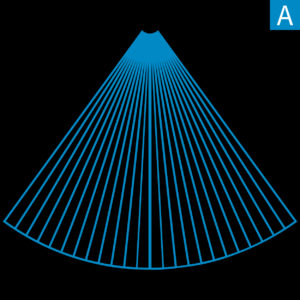

ZONE Sonography Technology (ZST) is a revolutionary, software-driven approach to acoustic data acquisition and image formation that breaks the barriers of conventional ultrasound imaging. Using a variable number of large imaging “ZONES”, ZST is capable of utilizing up to 90% more ultrasound data than conventional ultrasound imaging platforms and at speeds 10 times faster. This expanded acoustic data set is retained and processed by patented high-speed digital processing techniques and software algorithms that are radically different from slow and cumbersome hardware-based imaging methods.